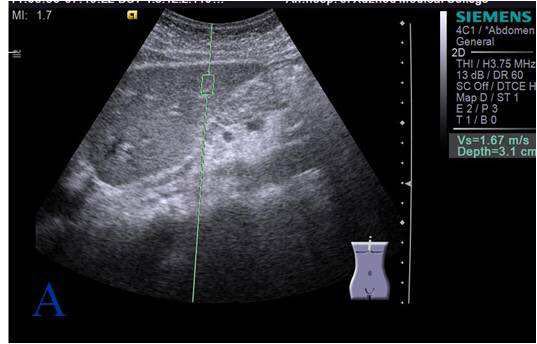

男,45岁,上腹痛,据按,无伴随症状,轻度精神分裂症,服药10年

常规彩超腹部超声无明显异常声响,加做弹性成像,如图所示